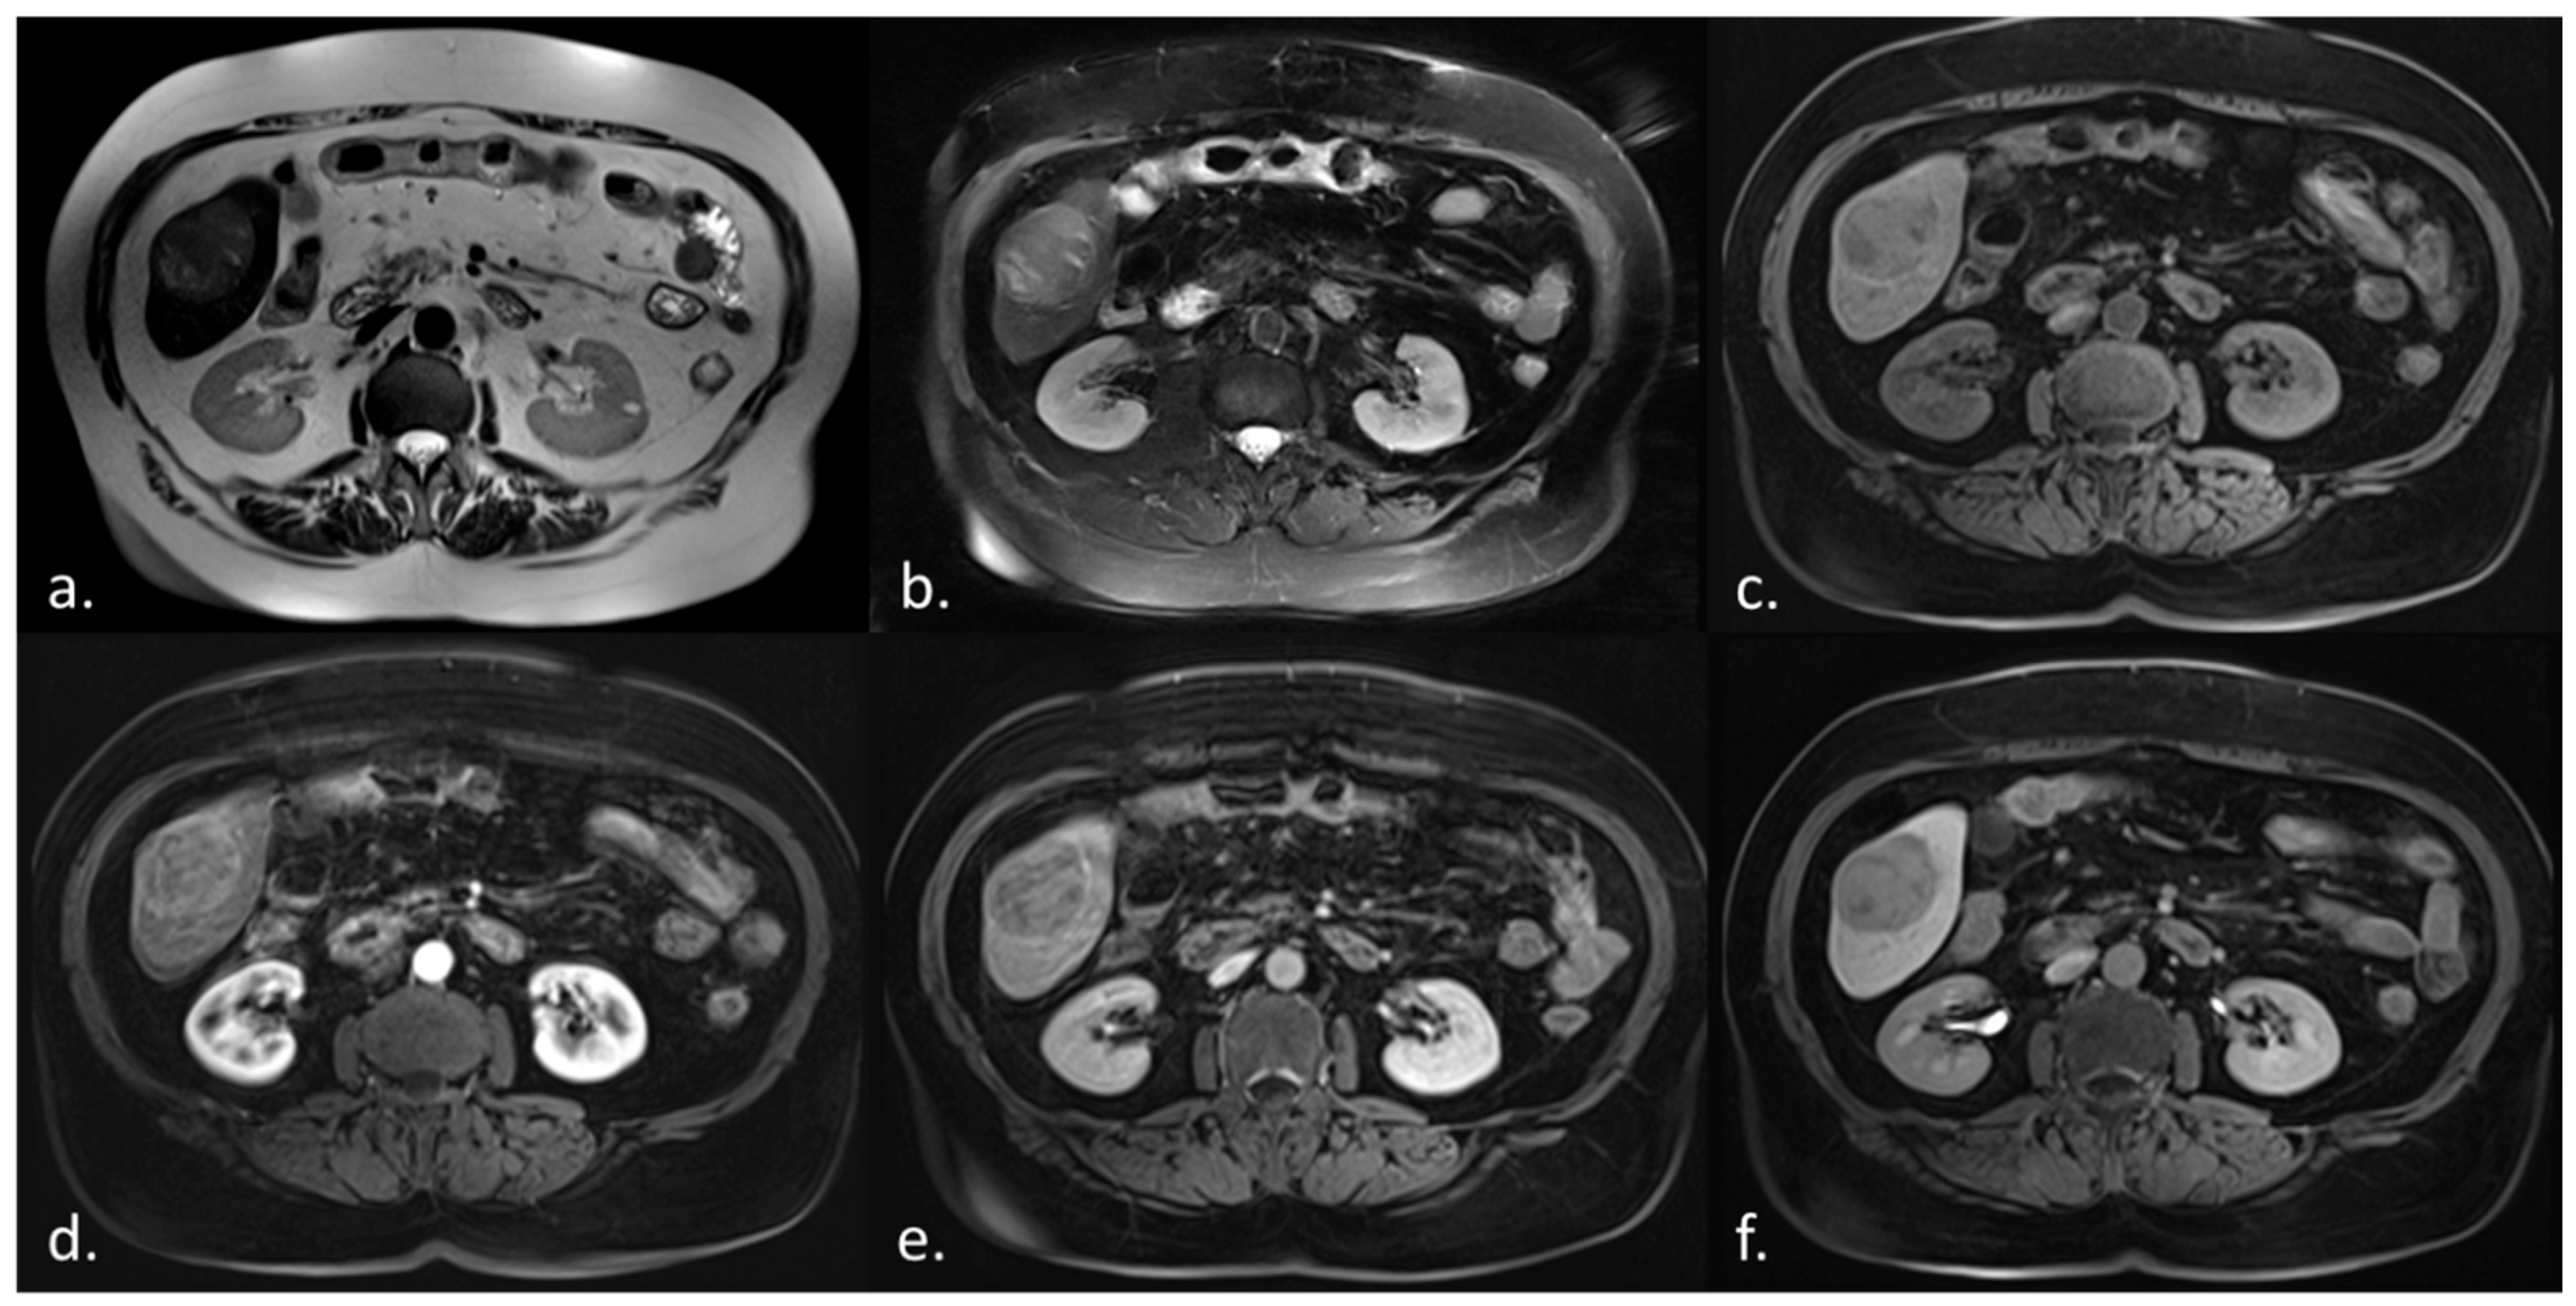

2.4. Magnetic Resonance Imaging (MRI)

2.5. Image Data Preparation